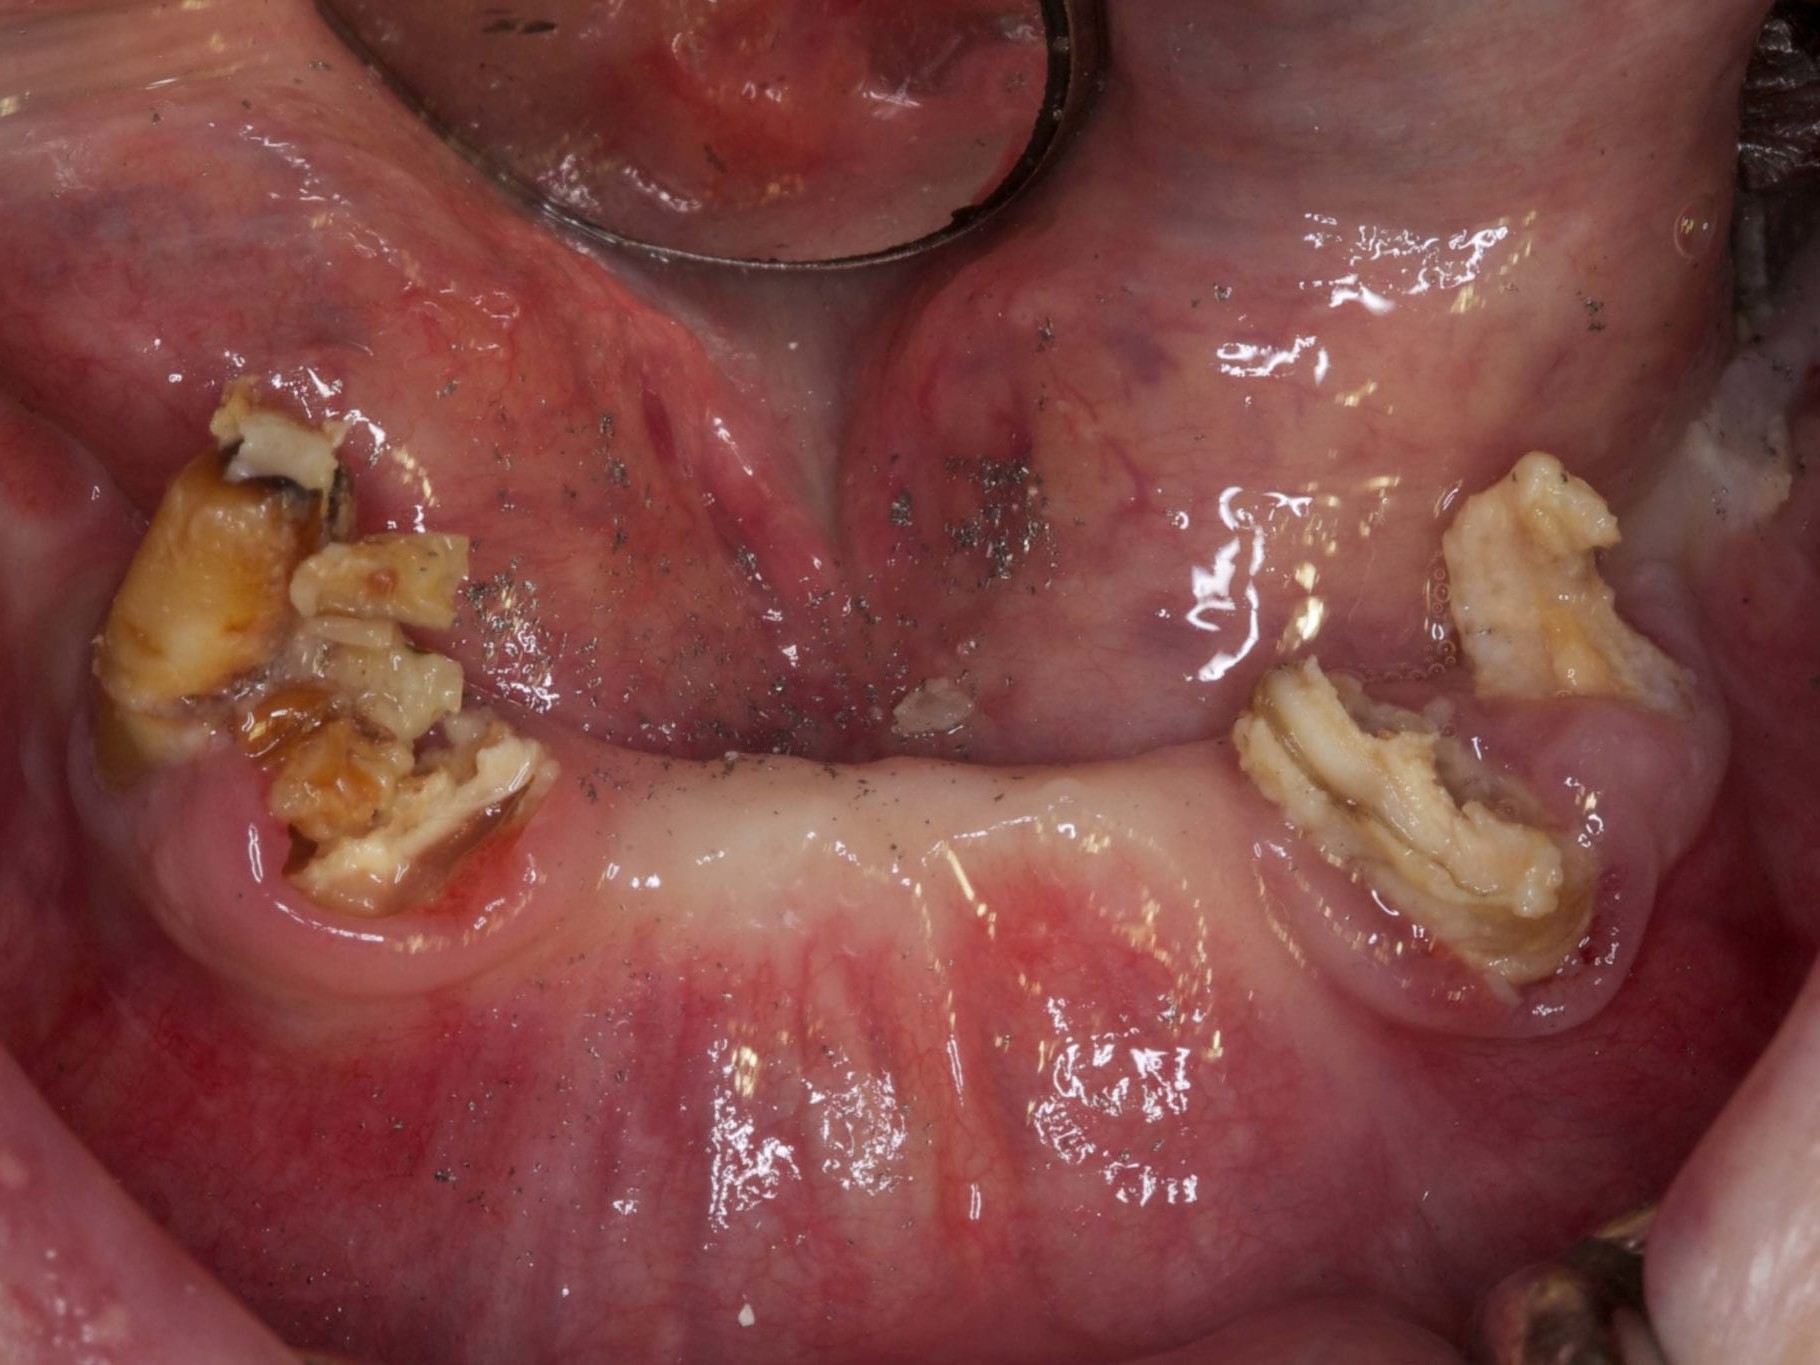

Bei dem nachfolgenden Fall handelt es sich um eine 73-jährige Nichtraucherin im guten allgemeinen Gesundheits- und Ernährungszustand. Die Patientin steht in keiner medikamentösen Behandlung und wies keine Allergien auf. Die Patientin kam 2012 zu uns in die Behandlung. Damals zeigte sich bei ihr eine festsitzende aber insuffiziente Rehabilitation im Unterkiefer, wobei die beiden Blattimplantate die gesamte Rekonstruktion trugen. Die Unterkieferzähne, die bisher die anteriore Abstützung bildeten, waren unter der prothetischen Versorgung kariös zerstört (Abb. 1). Seitens der Patientin bestand der Wunsch nach hochwertiger Rehabilitation des Unterkiefers möglichst mit einer Sofortversorgung. Eine zwischenzeitliche Versorgung mit einer schleimhautgetragenen Interimsprothese schied aus. Darüber hinaus war für die Patientin wichtig, eine möglichst geringe Belastung durch die anstehende Behandlung zu erfahren. Der Oberkiefer war mit eine herausnehmbaren Vollprothese rehabilitiert. Zur exakten Vorhersagbarkeit der Implantatpositionen wurde ein DVT angefertigt. Im Anschluss erfolgte eine gemeinsame Planung der chirurgischen sowie prothetischen Implantatposition im Team, bei der Chirurg, Prothetiker und Zahntechniker im ständigen Dialog standen (Abb. 2 und 3).

Für die Allgemeinanästhesie erfolgte zunächst die zusätzliche Gabe eines typischen Infiltrationsanästhetikums. Intravenös wurde unmittelbar präoperativ das Antibiotikum Clindamycin 600 mg gegeben. Abbildung 7 zeigt die klinische Ausgangssituation linksseitig. Nach der vorsichtigen Durchtrennung der Brückenkonstruktion (Abb. 8) jeweils vor der Krone auf den Blattimplantaten und Entfernung der nicht erhaltungswürdigen Zähne 44 bis 33 samt ihrer Überkronung (Abb. 9) wurde der Mukoperiostlappen vestibulär wie lingual passend zur erstellten Schablone präpariert und die Bohrschablone in ihrer finalen Lage eingebracht (Abb. 10). Zunächst erfolgte die Insertion der angulierten Implantate Ankylos ® C/X-Implantate (Durchmesser 3,5 mm) der Länge 14 mm in regio 034 (Abb. 11 und 12) und 044. Danach wurden in den Positionen 032 und 042 jeweils ein weiteres Ankylos ® C/X –A-Implantat mit gleicher Länge und Durchmesser inseriert (Abb. 13). Sämtliche entfernten Knochenpartikel und auch Bohrspäne wurden akribisch asserviert. In den Positionen 032 und 042 wurden Ankylos ® Balance Basisaufbauten C/ (GH 3,0 / Ø 5,5 mm, Kopfhöhe 2,4 mm) mit 15 N/cm eingeschraubt. Anschließend hat der Zahntechniker mittels der Ankylos ® Modellierhilfskappenfür den Balance Basisaufbau Retentionskappen hergestellt, die mit 25 N/cm eingebracht wurden (Abb. 14). Am Implantat regio 042 wurde der Knochen in Schalentechnik nach vestibulär aufgebaut (Abb. 15)⁹,¹⁰. Im nächsten Schritt haben wir die angulierten Ankylos ® Balance Basisaufbauten C (nicht indexierte Abutments) in Regio 034 und 044 (GH 3,0, A30 / Ø 4,2 mm, Kopfhöhe 1,3 mm) ausgerichtet und ihren spezifischen Vorgaben entsprechend eingebracht (Abb. 16). Nachdem sich alle erforderlichen prothetischen Implantatbauteile in situ befanden (Abb. 17), erfolgte die Überprüfung und geringfügige Anpassung des im Vorfeld digital erstellten Sofortprovisoriums. Im Anschluss wurden die leeren Alveolen und Knochendefekte mit dem gewonnenen autologen partikulären Material aufgefüllt. Dann erfolgte der typische Naht-Wund-Verschluss mit Einzelknopfnähten eines resorbierbaren Nahtmaterials (Abb. 18). Nachdem die Patientin aus der Vollnarkose erwacht war und ihre motorischen Fähigkeiten wiedererlangt hatte, wurde das Sofortprovisorium eingesetzt und in Okklusion gebracht. In dieser Position wurden die Retentionskappen über ein selbsthärtendes fluoreszierendes kaltpolymerisierendes Paste-Kartuschensystem fixiert. Anschließend erfolgte die extraorale Versäuberung des Interimszahnersatzes. Nach Refixierung des Sofortprovisoriums in der Mundhöhle (Abb. 19 und 20) und dem Verschluss der Schraubenkanäle mit Kunststoff erfolgte die radiologische Kontrolluntersuchung (Abb. 21).